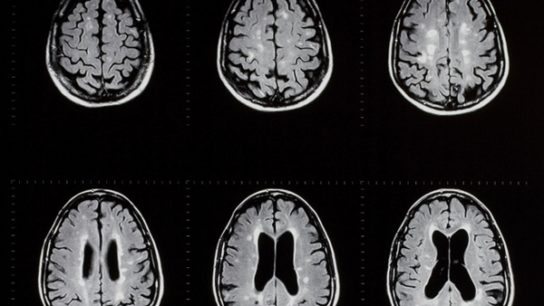

The 2021 MAGNIMS-CMSC-NAIMS provided updated consensus recommendations on MRI use in the management of multiple sclerosis.

A combination of clinical, imaging, and neuropsychological examinations may aid in MS disease progression prognostication.

A proper MS diagnosis can only be made after obtaining imaging from the entire brain and understanding the clinical context.